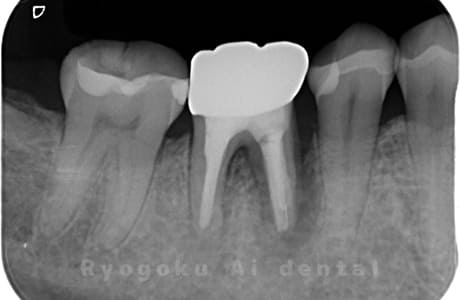

Case07

-

- 原因

- 右下6番歯根破折

- 治療内容

- インプラント治療

- 治療費用

- 約600,000円

右下の腫れが治らないとの事でご来院された患者様です。歯が割れていたため、抜歯を行い、骨に代わるお薬を入れ、インプラントを埋入致しました。経過良好で大変満足していただけました。

<リスク・副作用>

治療後、痛みや違和感、出血、腫れなどが出る事があります。喫煙者、糖尿病などの方の場合、歯が生着しない場合があります。